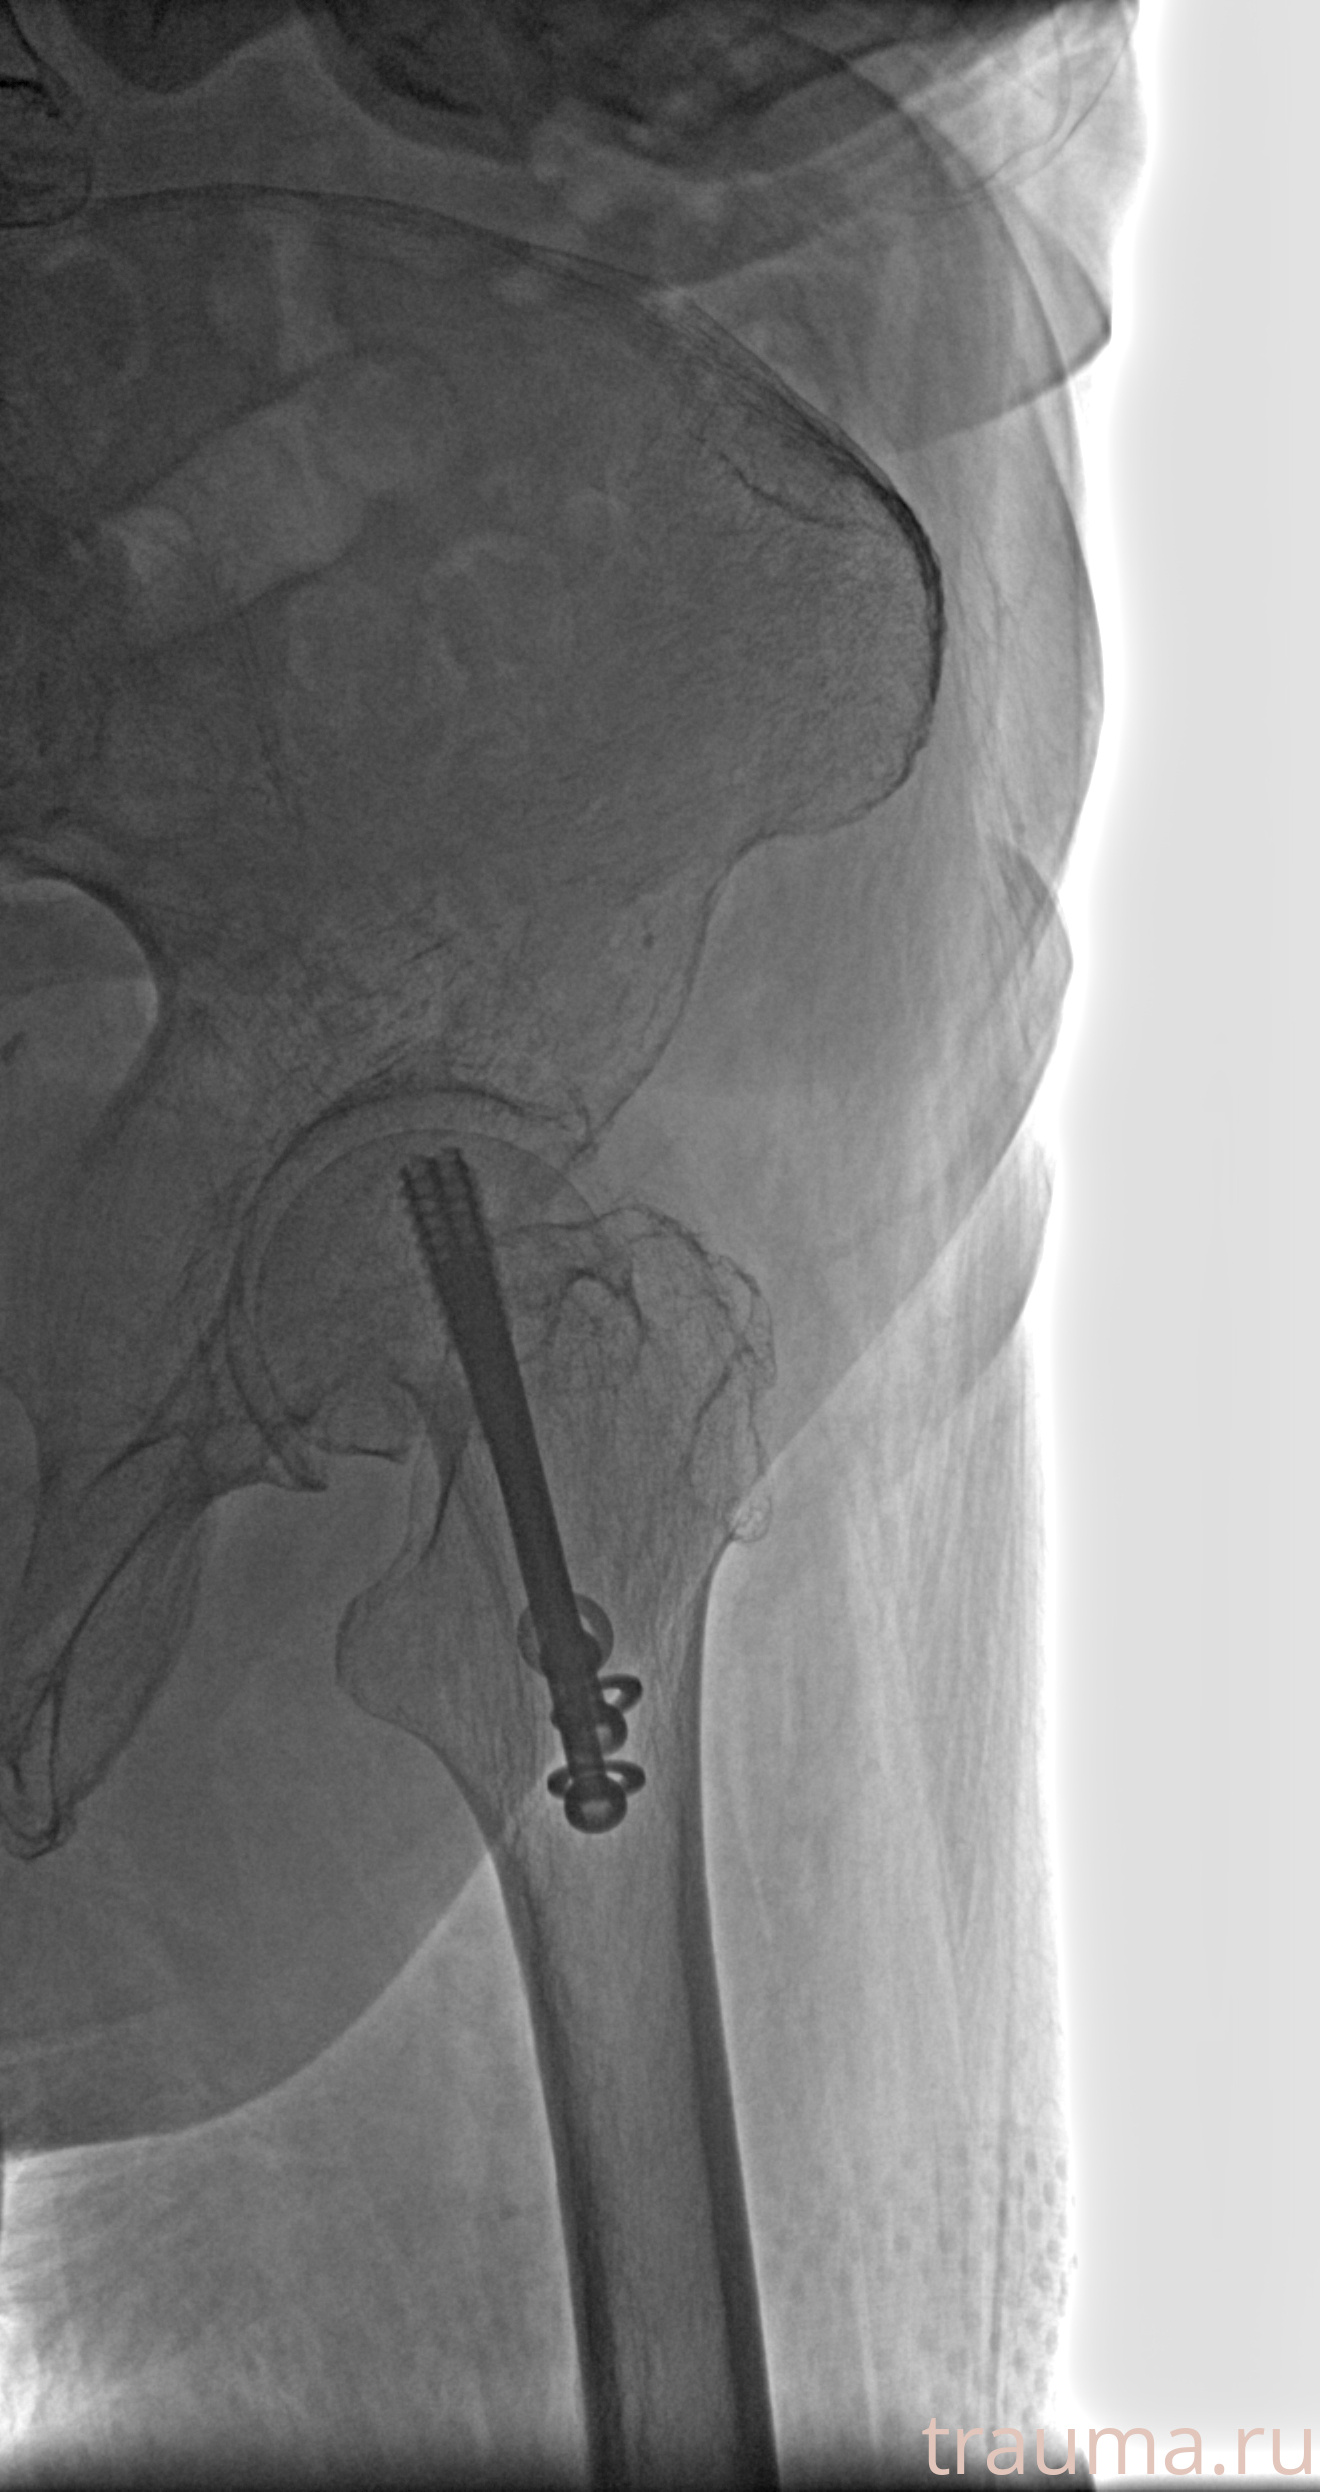

Рентгенограммы

Рентген на дому: по вашему адресу приезжает врач-рентгенолог, травматолог-ортопед с мобильным рентгеновским аппаратом, проводит диагностику травмы или заболевания, делает необходимые рентгенограммы, дает рекомендации по дальнейшему лечению. Получить качественные снимки в домашних условиях возможно благодаря уникальной методике, разработанной МосРентген Центром для института  Склифосовского